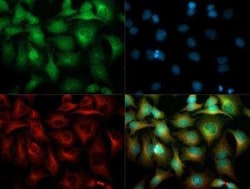

| Immunohistochemistry (Paraffin), Western Blot, Immunocytochemistry | |